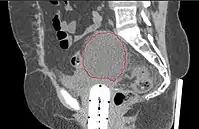

- Postoperative Lymphocele